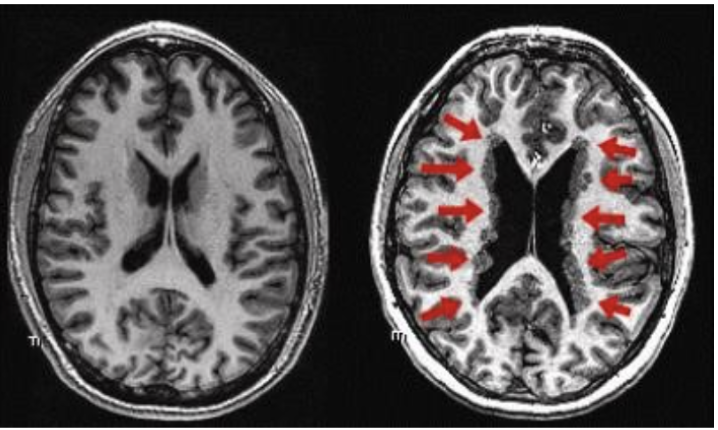

What can go wrong with differentiation and migration? Specifically mention mutations of the cytoskeleton

Cytoskeleton mutations affect neuroblast ability to migrate

Eg: loss of doublecortin protein in females -> leads to Periventricular Heterotopia (clumps of abnormally located grey matter) → severe learning difficulties, Epilepsy.

Doublecortin protein is on the X-linked DCX gene, so females more commonly affected + is a dominant allele